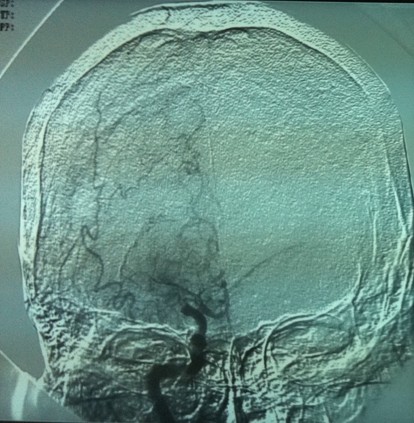

造影见右侧颈内动脉成残端